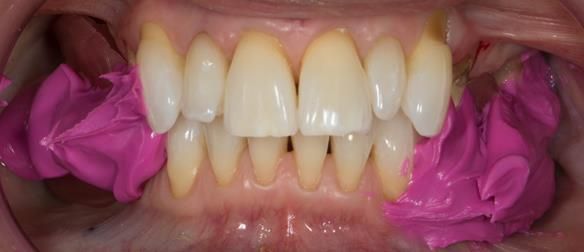

This newsletter describes in step by step detail Angela's transition through immediate partial dentures to crown supported definitive metal based dentures.

This 58 year old woman was referred to me by her general dental practitoner for treatment.

The clinical situation and treatment process is shown in detail below with photographs. I (Finlay Sutton) provided the clinical work and Rowan Garstang provided the technical work.